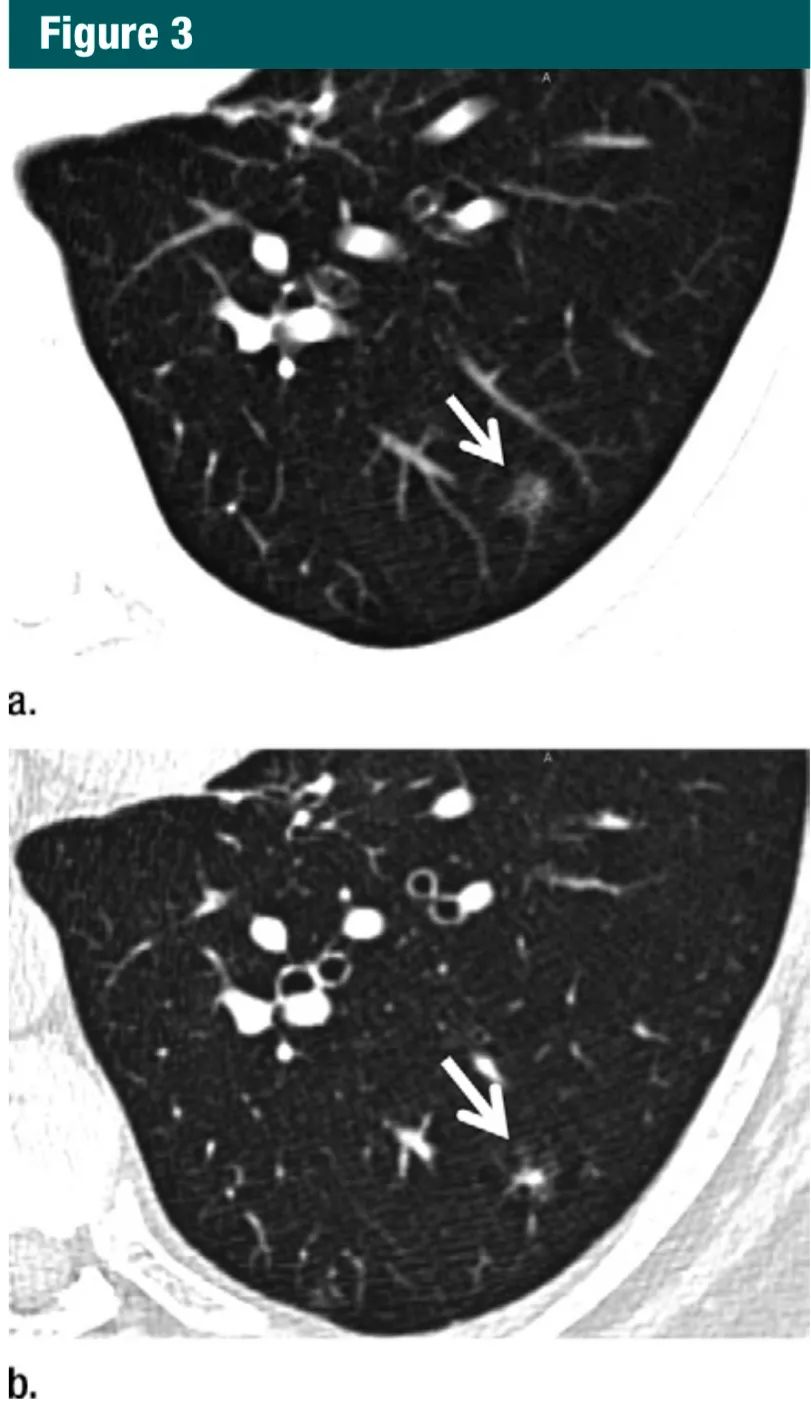

图3:a.5mm层厚CT显示左下叶一纯磨玻璃结节(箭头);b.同一部位和层面的1mm层厚CT显示,这是一个可疑的部分实性结节,其内有空泡(箭头)7Gc帝国网站管理系统